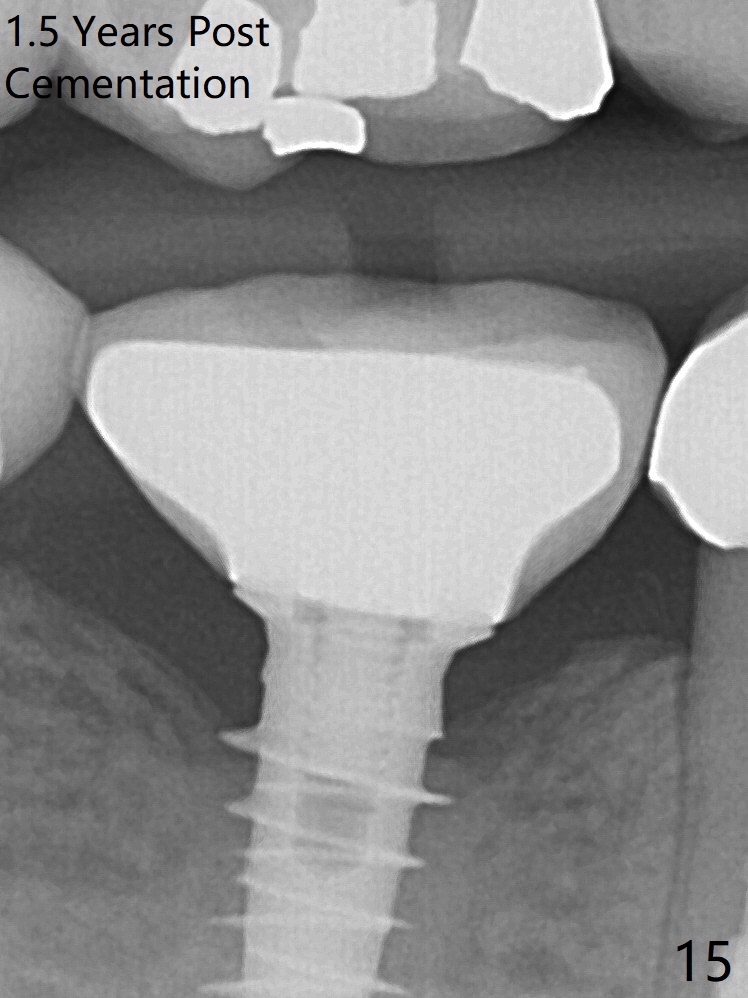

The bone density immediately around the implant appears to increase 1.5 years post cementation (Fig.15,16).